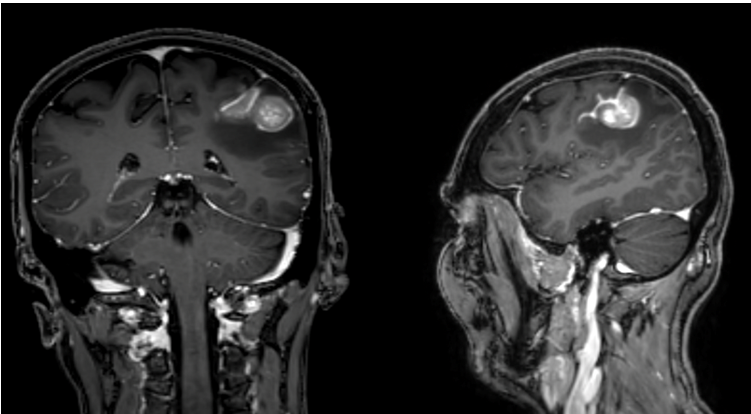

We present the case of a 47-year-old female patient, right handed, known to have a history of left breast mass to which she underwent bilateral mastectomy 6 years prior to presentation with pathology showing Lobular carcinoma in situ, ER, PR, and HER2 positive, with 20% Ki67 to which she received chemotherapy and hormonal therapy with no recurrence on regular follow up. She presented for dizziness and headaches to which MRI brain was done and showed left parietal ill-defined solid enhancing cortical tumor measuring approximately 2.3x 2.2 x 3.3 centimeter with strong contrast enhancement with surrounding vasogenic edema that has increased in size since previous examination causing mass effect on the adjacent sulci, involving the left post central gyrus (Figure). There is also associated leptomeningeal enhancement along the left post central sulcus extending inferiorly to the left superior temporal gyrus. The differential diagnosis included lymphoma versus metastasis. PET scan was negative for any lesion other than that in the brain. Lumbar puncture was done to rule out lymphoma and turned out to be inconclusive. Patient had intact neurological examination with no signs of Gerstmann syndrome. Left parietal craniotomy for tumor biopsy/resection was done. An inverted U skin incision was done, intraoperative ultrasound was used to confirm the lesion location. Tans-gyral resection was done using bipolar and micro-scissors. Fresh frozen was taken and was read by pathologist as metastatic carcinoma. Decision was made to continue with tumor resection. A clear plane was identified between the lesion and the normal brain and gross total resection was achieved. Post op pathology showed metastatic carcinoma with mucinous features consistent with breast origin.

Figure 1